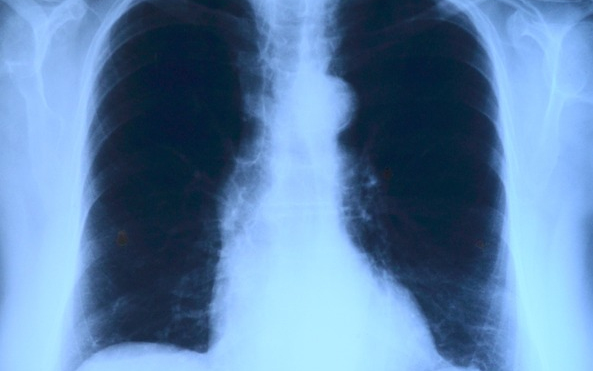

Elvégezték az országban az első tüdőverőér-tágítást

Az országban elsőként a Debreceni Egyetem Klinikai Központjában végeztek tüdőverőér-tágítást - közölte a felsőoktatási intézmény sajtóirodája kedden az MTI-vel.

A nemzetközi orvoscsoport múlt hét szombaton két betegnél hajtotta végre a beavatkozást, amellyel a tüdőerek magas vérnyomását csökkentették. Mindkét páciens krónikus thromboembóliás pulmonális hipetróniában szenvedett, amely súlyos nehézlégzést, kisebb fizikai terhelhetőséget és akár eszméletvesztést is okozhat. Az első hazai ballonos pullmonális értágítást (BPA) Irene Lang professzor, a bécsi Allgemeines Krankenhaus (AKH) kórház II. Belgyógyászat-Kardiológiai osztályának vezetője és tanítványa, Christian Gerges végezte a debreceni kardiológiai és szívsebészeti klinika intervenciós kardiológusainak közreműködésével - olvasható az egyetem közleményében.

A nagy szakértelmet és türelmet igénylő, komplex katéteres eljárást egy 59 éves férfinál és egy 82 éves nőnél végezték el. A 2-3 órás beavatkozás során a tüdő véráramlását akadályozó vérrögöket ballonnal kitágították, így az áramlási akadály mérséklődött, a tüdőerekben pedig csökkent a nyomás, ezzel együtt a szív terhelése is.

A módszert a világon először 1988-ban alkalmazták, az első nagyobb betegszámú vizsgálatot 2001-ben publikálták, 2004-től pedig elsősorban Japánban tökéletesítették az eljárást, amely azóta az Egyesült Államokban, Norvégiában, az utóbbi évtizedben pedig Európa más országaiban is egyre elterjedtebb lett.

A közleményben hangsúlyozzák: A Debreceni Egyetem szakemberei bíznak benne, hogy az eljárást Lang professzor és munkatársai, valamint a Klinikai Központ orvosai segítségével sikerül meghonosítani Magyarországon is. A betegek életében ugyanis jelentős változást hoz a BPA-beavatkozás, a kezelés következtében csökkennek a fulladásos panaszok és nő a fizikai terhelhetőség.

A módszer nagy előnye a rövid felépülési idő, hiszen a műtét utáni kétnapos intenzív megfigyelést követően a betegeket akár már a harmadik nap hazaengedhetik. Az első magyarországi ballonos tüdőverőér-tágításon átesett betegek jól vannak, kedden már el is hagyhatták a klinikát - zárul az egyetem közleménye.